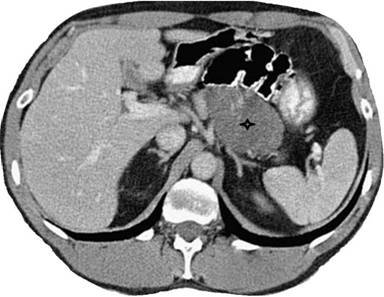

CT imaging has been attempted by several authors to evaluate pancreatic lymphoepithelial cysts with variable descriptions in the literature. For instance, some authors have characterized these lesions as well-circumscribed, low attenuating masses with thin enhancing rims, septations and focal calcifications [34]. On the other hand, Toumi et al. [13] described pancreatic lymphoepithelial cysts on CT scan as lobulated, non-enhancing and sharply demarcated lesions with focal calcifications, often in the absence of pancreatic ductal dilatation or atrophy (Figure 1). In addition, while most cases of lymphoepithelial cysts are either multicystic or unilocular with thin septations [34], the lymphoepithelial cyst case reported by Neyman et al. (2005) was not only unilocular, but also lacked septations, clear wall enhancements, or regions of fat attenuation [35]. Thus, pancreatic lymphoepithelial cysts may have papillary projections, small solid components, wall calcifications and/or thin wall enhancements on conventional CT imaging [26, 34]. This variation has led some authors to argue that three-dimensional computed tomography (3D-CT) scan, rather than the conventional scan, may be better suited to differentiate lymphoepithelial cysts from other lesions of the pancreas [35]. So far, this assertion has been supported by a recent study which showed that when compared to serous cystadenomas and mucinous cystadenomas, lymphoepithelial cysts had a predominantly extra-pancreatic 3D location and higher precontrast CT attenuation. Moreover, they were noted to be smaller and more frequently microlobulated than mucinous cystadenomas [36].

|

Figure 1. An axial CT image showing a large, hypodense lymphoepithelial cyst with internal septations within the tail of the pancreas. (Reproduced with permission from Toumi et al. [13]). |